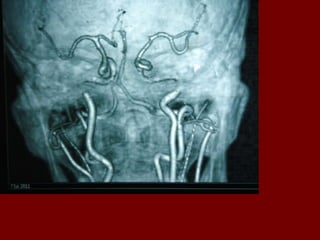

A V malformation Lesions of the cerebral vasculature develop such that blood flows directly from the arterial system to the venous system without passing through a capillary system. The arteriovenous (AV) shunt is the definitive characteristic of these lesions.

AVMs are considered congenital lesions and are characterized by a failure of the embryonic vascular plexus to fully differentiate and develop a mature capillary bed in the affected area  Molecular biologic factors are thought to be important to AVM development. These may include vascular endothelial growth factor (VEGF) and basic fibroblast growth factor (bFGF). Tissues adjacent to the AVM may be persistently mildly hypoxic because the malformation may steal blood from adjacent healthy tissue, further promoting angiogenesis.

Cerebral angiography provides definitive diagnosis. It documents a functional AV shunt; however, because it is an invasive test, it is not performed as the first imaging study. Cerebral angiography also allows grading of the AVM via the following Spetzler and Martin criteria.

Cerebral angiography providesdefinitive diagnosis. It documents a functional AV shunt; however, because it is an invasive test, it is not performed as the first imaging study. Cerebral angiography also allows grading of the AVM via the following Spetzler and Martin criteria.